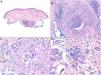

Histopathology. Histopathologic findings include a dermal infiltrate of small atypical lymphocytes (T helper immunophenotype: CD3+, CD4+, and CD8− ) that can extend into the subcutaneous tissue (Fig. 15B,C) and is accompanied by numerous multinucleated giant cells (Fig. 16A,B) showing elastophagocytosis and lymphophagocytosis (Fig. 16C,D). Findings in early-stage disease are similar to those seen in conventional mycosis fungoides. Polymerase chain reaction shows T-cell receptor gene rearrangement.34

Granulomatous slack skin. A, Lymphoid infiltrate in the dermis with numerous scattered multinucleated giant cells (H&E, original magnification x40). B, Lymphoid infiltrate in the septae of the subcutaneous tissue with multinucleated giant cells (H&E, original magnification x40). C, Detail of a giant cell with lymphophagocytosis (H&E, original magnification x200). D, Fragmentation and loss of elastic fibers (orcein x100). H&E indicates hematoxylin-eosin.